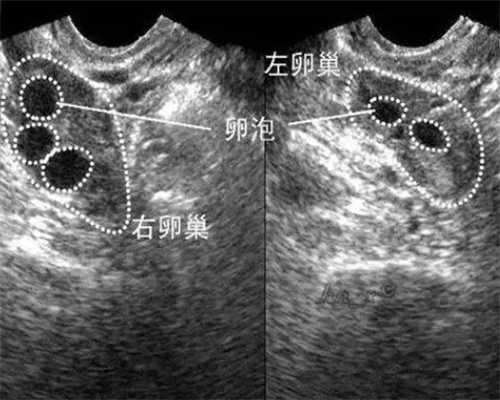

通过试管婴儿怀上龙凤胎其实也并不是想象中的那么容易的,因为做试管婴儿即使是怀上一个孩子都是有成功率的,怀上双胞胎其实也是比龙凤胎的成功率大一些的,因为不用考虑性别,也有可能通过试管婴儿怀上的双胞胎呀可能是龙凤胎的可能。

先不考虑能不能进行性别的选择合不合法,即使是做第三代试管婴儿做龙凤胎,如果是移植两枚胚胎,一个男胚和一个女胚,大家要知道如果有一个胚胎没有着床成功,可能就会出现怀上一个孩子,但这个孩子的性别自己也是未知的,如果是移植三枚胚胎,为了母体的考虑,都成活的话其实还是会进行减胎的,所以就会出现不知道是不是龙凤胎还是双胞胎的情况,如果能接受这些风险才能进行的。